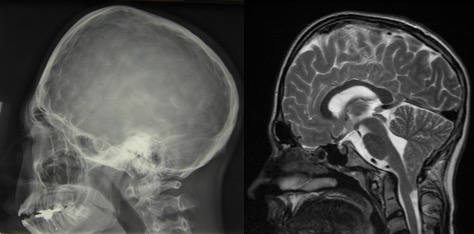

- les craniosténoses, surtout celles qui impliquent les sutures lambdoïdes et la sagittale (Mercedes-Benz syndrome)

hypophosphatasie avec fermeture multisuturaire réalisant un aspect d’oxycéphalie associée à un engagement tonsillaire chronique - de nombreuses maladies du squelette